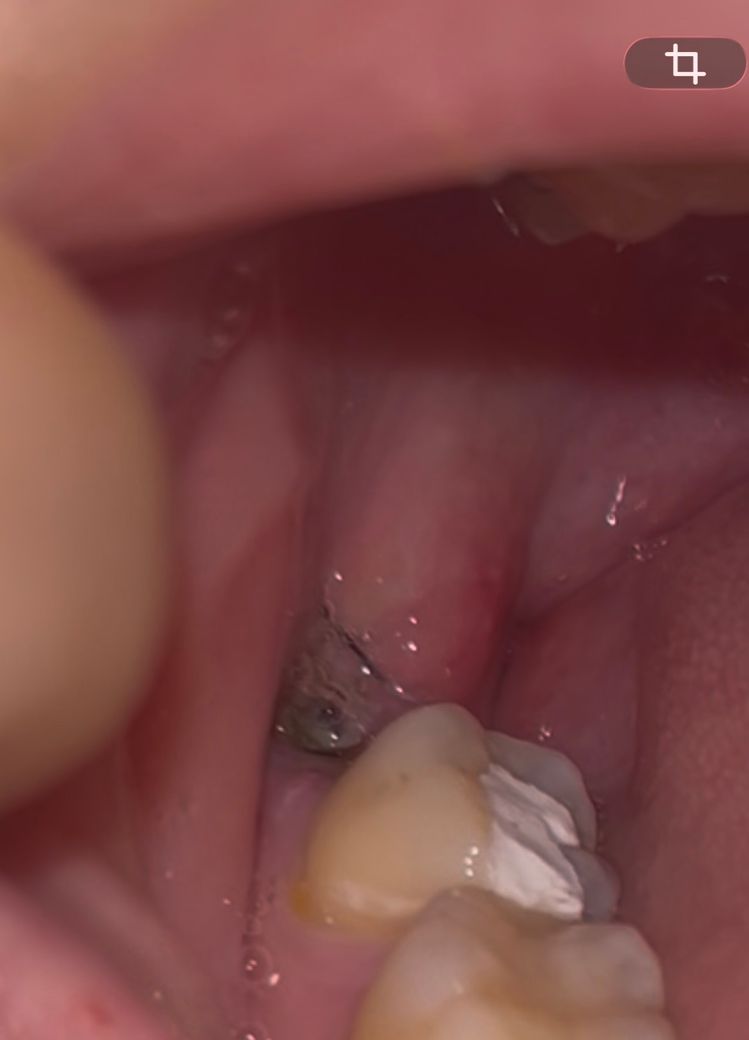

사랑니 발치한 자리에 음식물이 낀 건지 뭔지 모르겠어요ㅜㅜ

근데 먹고 양치하고 확인해보니 사랑니 발치한 자리에 흰색으로 뭐가 낀 것처럼 되어있습니다

하필 음식으로 계란찜을 먹어서 음식물이 낀 건지 회복되는 과정 중 생긴 건지 모르겠어서요ㅠㅠ

찾아보니 흰색 조직이 생기는 경우도 있다 해서 함부로 빼도 될지 모르겠습니다

사진으로 봤을 경우에는 사랑니를 발치한 부위에 음식물이 들어가 있는것이 맞는것으로 보입니다.